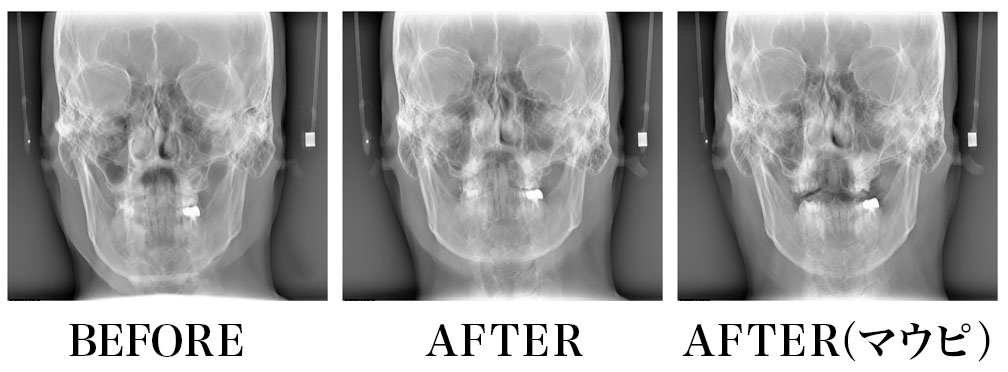

主訴:面長・頬のコケ・頬骨の出っ張り・食いしばり

内容:歪み小顔矯正42フル矯正

術後:初回矯正で面長が改善されて頬のコケと

出っ張りが取れた。

今後のプラン:ミューイング(舌体操)と

顔面整骨マウスピースで矯正位の維持と骨の安定を努めてもらい次のデザインを目指す。くいしばりや姿勢など、日常生活でも気をつけて頂く